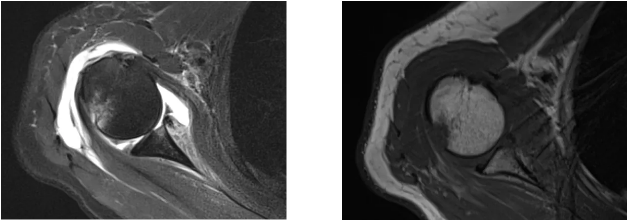

病例2

病史摘要:女性,65歲,跌傷致右肩活動(dòng)受限9天。

MR圖示:右側(cè)肱骨頭后上部局部明顯凹陷,骨皮質(zhì)欠光整,周圍見片狀壓脂高信號(hào)影(箭頭);前盂唇脫離移位;前下盂唇不連,局部骨質(zhì)分離(三角形);肱骨頭向前移位。